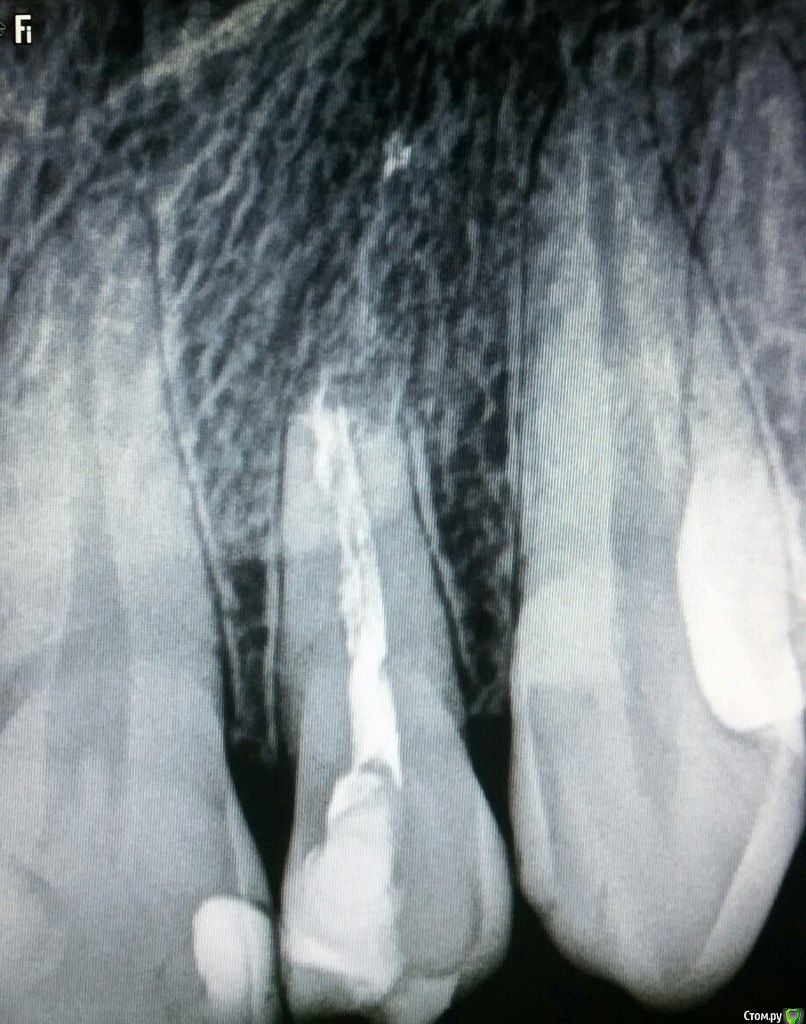

Mashelya Опубликовано 20 октября, 2015 Поделиться Опубликовано 20 октября, 2015 Добрый вечер, коллеги! Помогите советом. Пациент 27 лет обратился с жалобами на боли при кусании твердой пищи и сильном смыкании зубов в области 22. Боли появились несколько дней назад, зуб лечен эндодонтически много лет назад, причину (травма/не травма) пациент не помнит. Визуально: небольшой вестибулярный скол пломбы. Перкуссия 22 болезненна. Зуб неподвижен. Слизистая без изменений. На снимке: резорбция корня, следы материала в костной ткани. Отправила на кт. Ваше видение ситуации? Ссылка на комментарий

ARislanV Опубликовано 20 октября, 2015 Поделиться Опубликовано 20 октября, 2015 Если снимок не врет, то похоже что там заместительная резорбция. Т.е. идет резорбция корня с одновременным образованием кости на ее месте. И каких то достоверных методов лечения ее нету. Но все равно бы я попробывал бороться за зуб. Очистка, промывание, кальции на две недели, пломбирование гуттой. Только в следующий раз обьясните пациенту, что зуб сложный и в будущем скорее всего придется удалять, но вы попробываете лечить ( конечно за опред. плату). Ссылка на комментарий